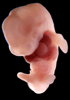

Carnegie Stage 17 (41 post-ovulatory days)

Most embryos at stage 17 are approximately 41 postovulatory days old and measure 11-14 mm in length. Distinguishing criteria for this stage include distinct digital rays in the hand plate, a rounded digital plate in the foot, a complete complement of hillocks on the mandibular and hyoid arches, distinct nasofrontal grooves, and a slight indication of a lumbar curvature.

This specimen does not represent normal development. The caudal nueral tube has failed to close properly.